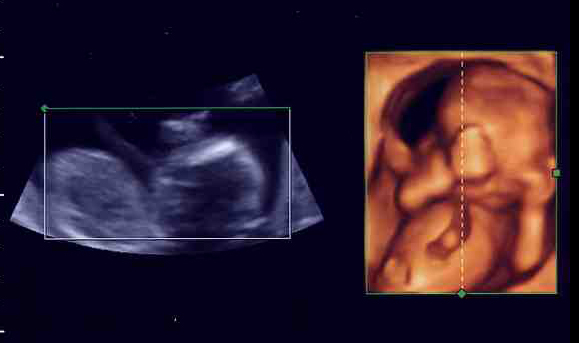

下の写真を見比べてみて。今までのエコー写真は白黒で、シルエットがぼんやり写るぐらい(左写真)。右の4D写真だと、「私」の手の指も、顔の輪郭も、臍帯まではっきり見えるでしょ?

先生の説明だと、モノが立体に見える「3D画像」を時間を追ってみられるから「4D」と呼ぶんだそうです。1秒間に6回画像が更新されて、映像を見ているみたいにリアルなんだって。手で顔をこすったり、あくびをしたり、足を握ったリ、キックしたり。しかめ面や微笑む顔まで、よーくわかるらしいの。ママの臍帯を握って安心している様子も見られちゃう(下写真)。ママは「ああ、お腹の中で生きてるんだなあ」って実感がわいて、とても感動するみたい。